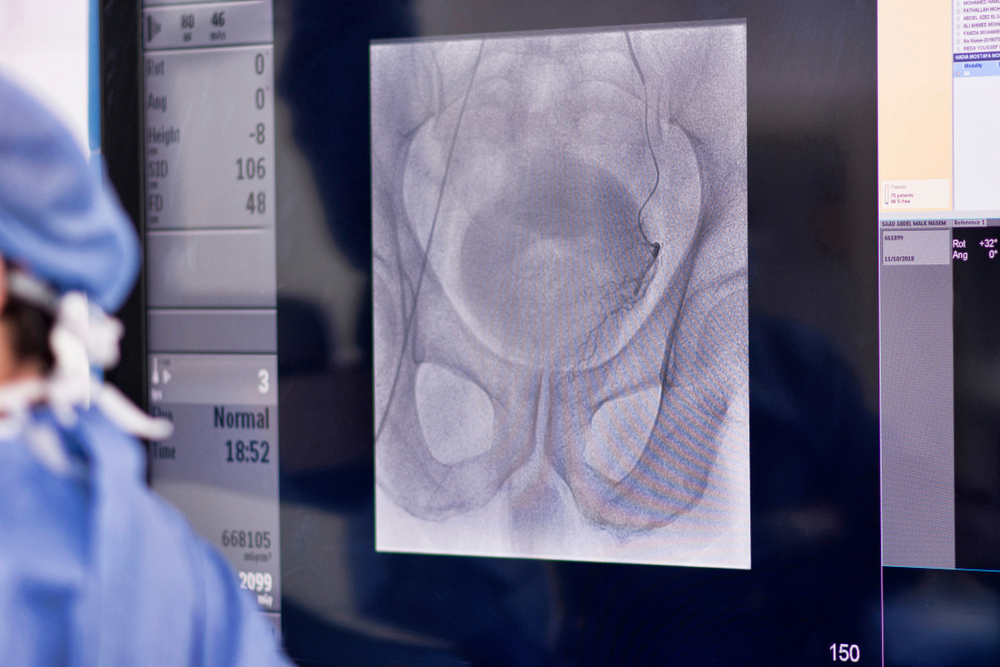

Interventional Radiology. Prostatic artery embolization (PAE)